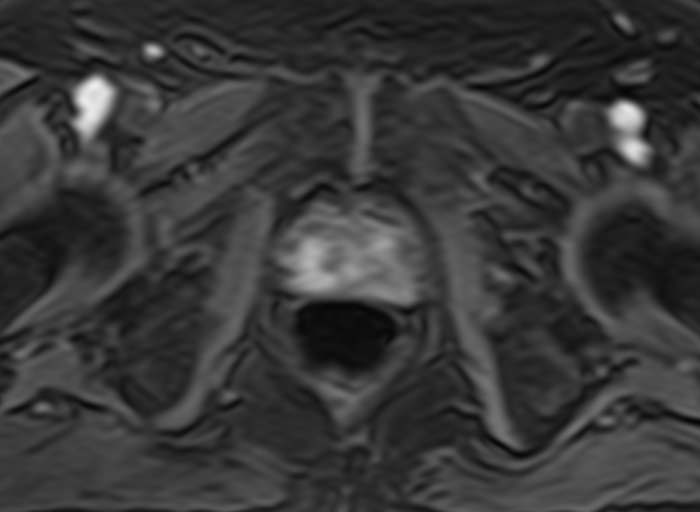

Простата расположена в труднодоступной для диагностики анатомической области, однако метод магнитно-резонансной томографии позволяет детально изучить структуру органа и окружающих ее тканей, включая семенные пузырьки (секреторные органы, вырабатывающие жидкую часть семенной жидкости) и семявыносящие протоки.

При подозрении на опухолевый процесс в предстательной железе в обязательном порядке проводится контрастное усиление. Это подразумевает внутривенное введение контраста, созданного на основе соединений металла гадолиния. Степень и характер накопления контрастного препарата в органах и тканях позволяет различать патологические процессы, в том числе диагностировать опухоли на ранних стадиях, что повышает шансы на успешное лечение.

В клинике «Доступная медицина» диагностика заболеваний предстательной железы выполняется при помощи современного высокопольного магнитно-резонансного томографа экспертного уровня TOSHIBA VANTAGE TITAN 1,5 Тесла. Аппарат производит сканирование в виде послойных тончайших срезов с шагом от 1 мм и преобразует их при помощи инновационных компьютерных программ в изображения трехмерного формата. Методика позволяет получить максимально полную картину о состоянии структуры простаты и окружающих тканей и поставить точный диагноз.